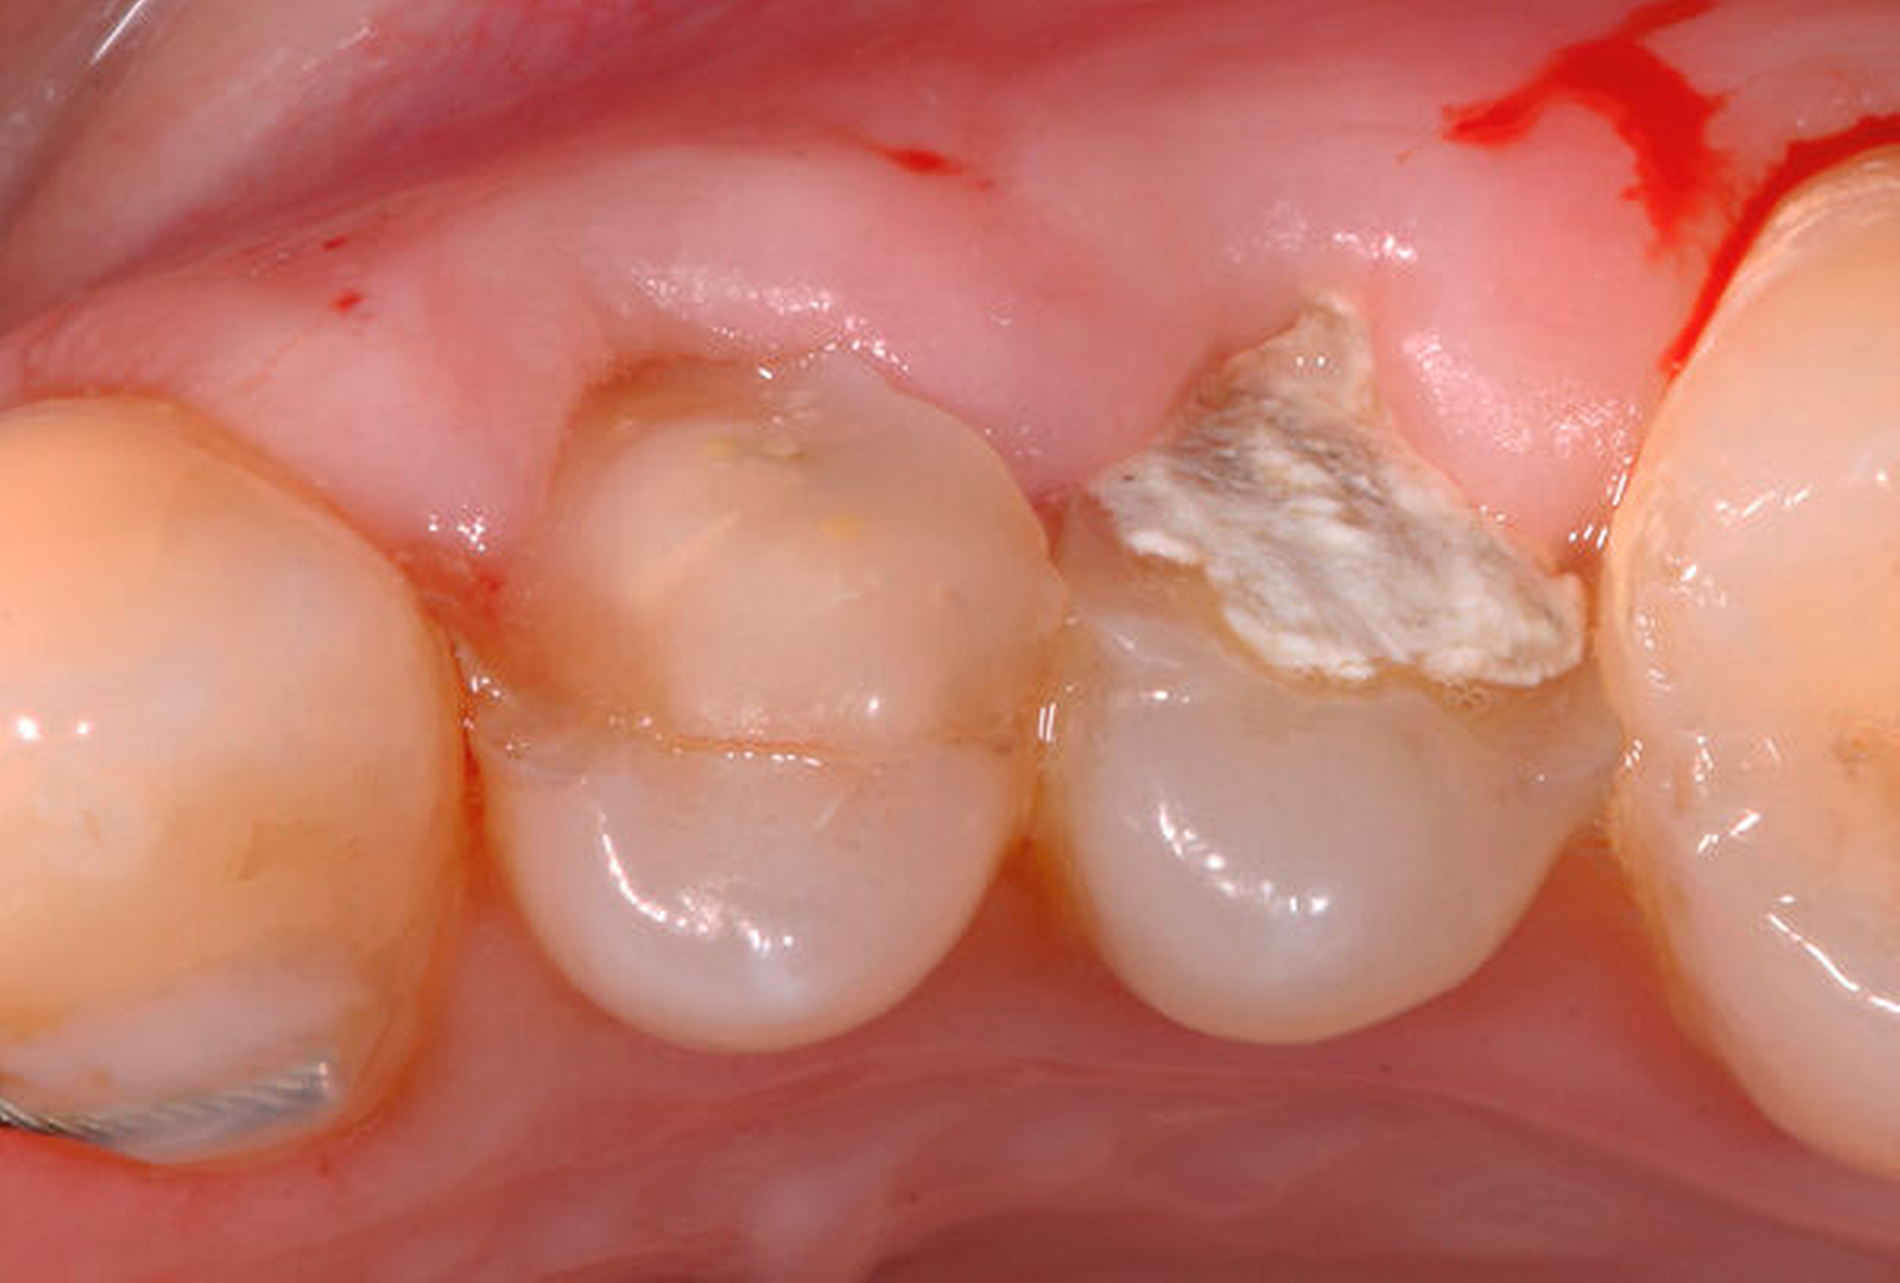

Traumatisierte Zähne mit tiefen, bis zum Alveolarknochen reichenden Defekten gelten als schwer zu restaurieren. In der Traumatologie betrifft dies Kronen-Wurzel-Frakturen oder zervikale Wurzelquerfrakturen. Zähne mit kariesbedingt hohem koronalem Zahnhartsubstanzverlust gehören ebenfalls dazu. Eine sichere Trockenlegung für den präendodontischen Aufbau und eine dichte Kofferdamanwendung sind bei derartig massiv geschädigten Zähnen kaum möglich. Adäquate endodontische Maßnahmen wären somit kaum durchführbar. Zudem gestalten sich sowohl direkte Kompositaufbauten als auch indirekte Versorgungen äußerst schwierig. Wird mit einem krestal gelegenen Restaurationsrand die biologische Breite unterschritten, verursacht dies chronische Entzündungsprozesse. Zudem ist bekannt, dass bei Überkronungen endodontisch behandelter Zähne ein „ferrule-design“ von 2 mm in gesunder Zahnhartsubstanz erzielt werden sollte [Naumann et al., 2018]. Dies sichert eine stabile koronale Restauration und vermeidet maßgeblich den frühzeitigen Retentionsverlust von Zahnersatz. Liegen Defekte vor, die eine Restauration nur unzuverlässig ermöglichen, kann eine Extrusion der Zahnwurzel sinnvoll sein. Hierbei wird der Bereich des tiefsten Zahndefekts durch die Koronalverlagerung möglichst weit iso- oder sogar supragingival positioniert, um somit eine sichere Restaurationsfähigkeit erzielen zu können. Die restaurative Versorgung bei Frontzähnen umfasst abhängig vom Ausmaß der koronalen Destruktion die direkte adhäsive Technik mittels Kompositfüllung oder laborgefertigtem Zahnersatz.

Eine weitere Möglichkeit, tief zerstörte Zähne möglichst schonend chirurgisch zu extrudieren, basiert auf axialen Zugsystemen (Abbildungen 2 bis 4). Diese erscheinen vorteilhaft bei sehr schwierigen Fällen, zum Beispiel bei Zähnen mit fehlendem Ansatzpunkt für die Zange sowie bei langen oder sehr ovalen Wurzeln. Axiale Zugsysteme ermöglichen die Übertragung von Zugkräften auf die Zahnwurzel, ohne die Alveole unnötig zu dehnen. Dazu wird eine spezielle Schraube in den Wurzelkanal eingebracht und das Gewinde der Schraube für eine ausreichende Friktion fingerfest eingedreht. An diese Schraube wird ein gerätespezifisches Zugsystem angelegt. Durch rein axial wirkende Zugkräfte werden traumatische Effekte auf Knochen und Wurzeloberfläche während der Zahnmobilisation minimiert. Gegebenenfalls können feine Luxatoren vorsichtig unterstützend eingesetzt werden. Im Tiermodell wurde an extrahierten und wieder replantierten Zähnen mit ovalem Querschnitt gezeigt, dass der Verlust von Zementoblasten auf der Wurzeloberfläche geringer ist, wenn ein axiales Zugsystem anstatt einer Extraktionszange verwendet wird.